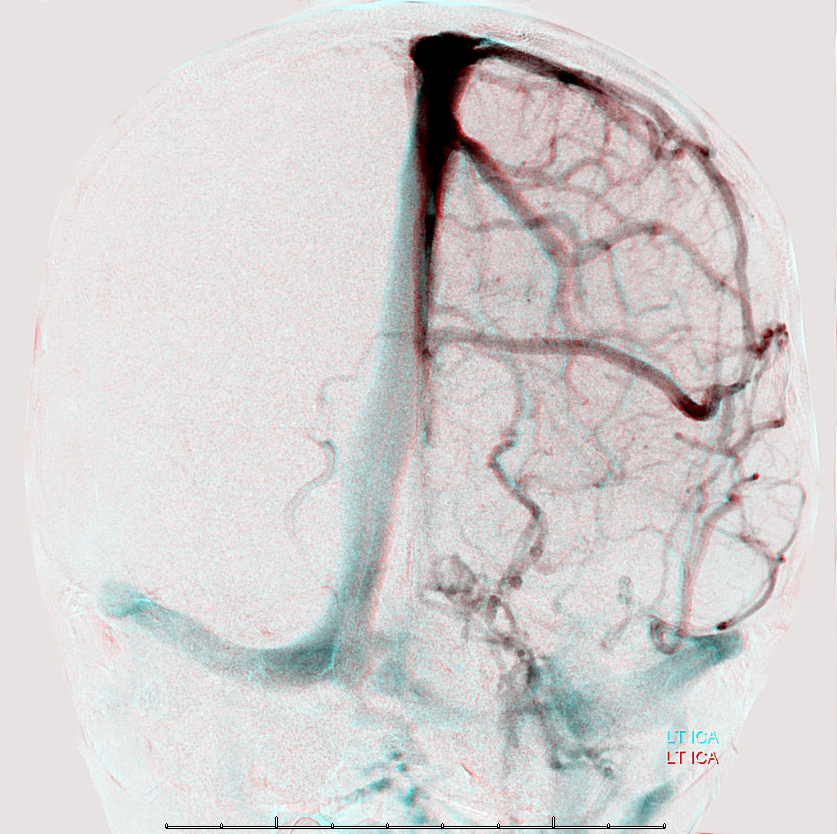

Following embolization, resection, recurrence (as frequently the case with childhood AVMs) and gamma-knife, things look good. Stereo, of course.

Following embolization, resection, recurrence (as frequently the case with childhood AVMs) and gamma-knife, things look good. Stereo, of course.